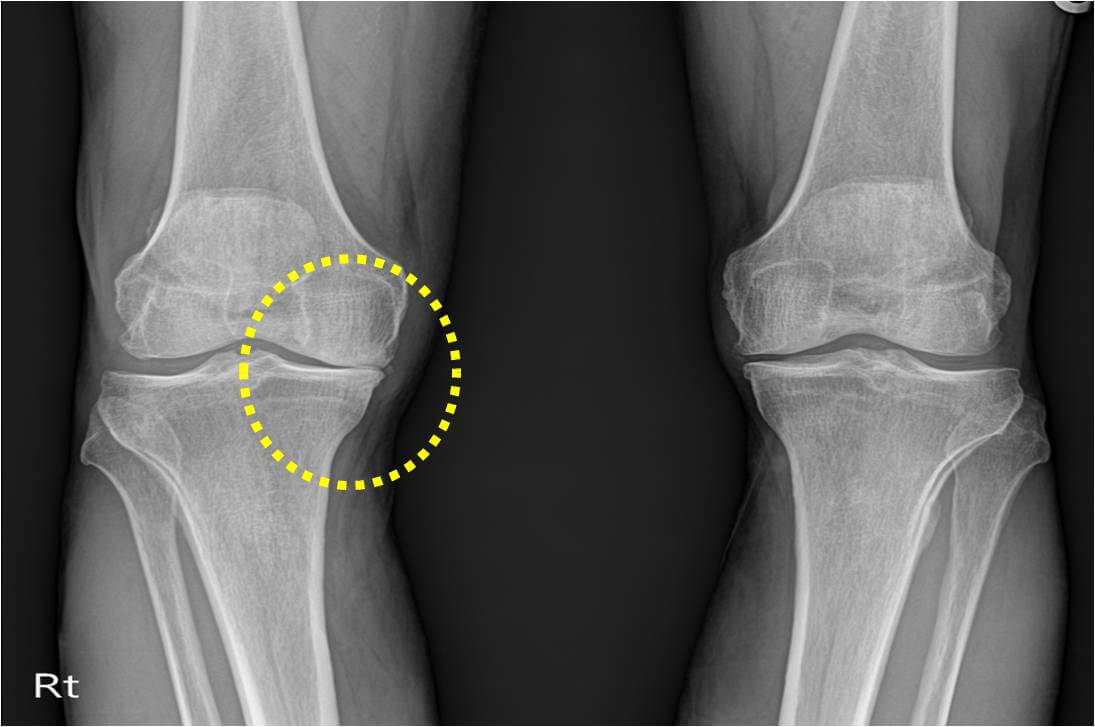

류마티스 관절염이란 우리 체내 면역체계에 이상이 생겨 관절 내에 염증이 생겨나게되고, 관절이 점차 파괴되는 증상이 지속되어 턱, 척추, 손, 발, 손목, 발목, 무릎 등의 관절에 영향을 미치는 만성질환을 말해요. 또한, 눈, 피부, 폐, 혈관 등에도 손상을 줄 수 있답니다. 퇴행성 관절염은 노화가 일어나면서 자연스럽게 관절에도 문제가 생기는 상태라고 볼 수 있으며, 류마티스 관절염은 노화와는 무관하게 자가 면역체계의 문제로 인하여 관절염이 생기는 상태입니다.

류마티스 관절염은 갑자기 시작되어 또한, 다수의 관절에 염증이 발생할수 있고, 보다 빈번히 점진적으로 시작되고 상이한 관절에 영향을 미치게 되어요. 보통 염증은 대칭적으로 인체 양쪽의 관절들이 일정하게 영향을 받으며, 류마티스 관절염은 어떠한 관절에도 영향을 미치지만 가장 흔한곳은 손, 손목, 손가락, 발, 발가락 또는 무릎, 어깨, 팔꿈치, 발목, 고관절 입니다.

류마티스 관절염 초기증상에서 흔한 증상으로써 관절을 싸고 있는 활액막에 염증이 발생하며 진행될수록 점차 주변 연골과 뼈로 염증이 퍼지게 되는데 그 결과 온몸의 모든 관절이 쑤시고 저리면서 뻣뻣해지는 것을 시작으로서 관절의 통증, 후끈거림, 압통과 같이 붓기가 발생해요. 보통 양쪽 관절에 이러한 증상들이 발생하게면서 손목, 팔꿈치, 무릎, 손가락, 발가락 부터 관절에 많은 양 발생한다고 해요.